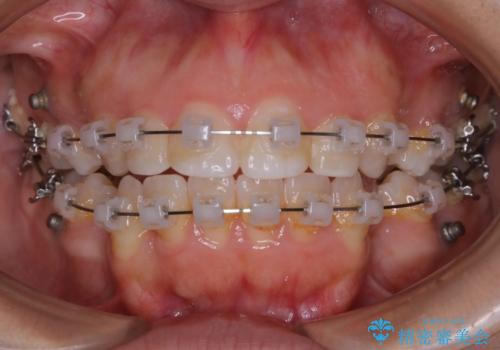

- 矯正装置

- ワイヤー(クリア装置)

- 治療期間

- 2年6ヶ月

- 治療回数

- 30回以上